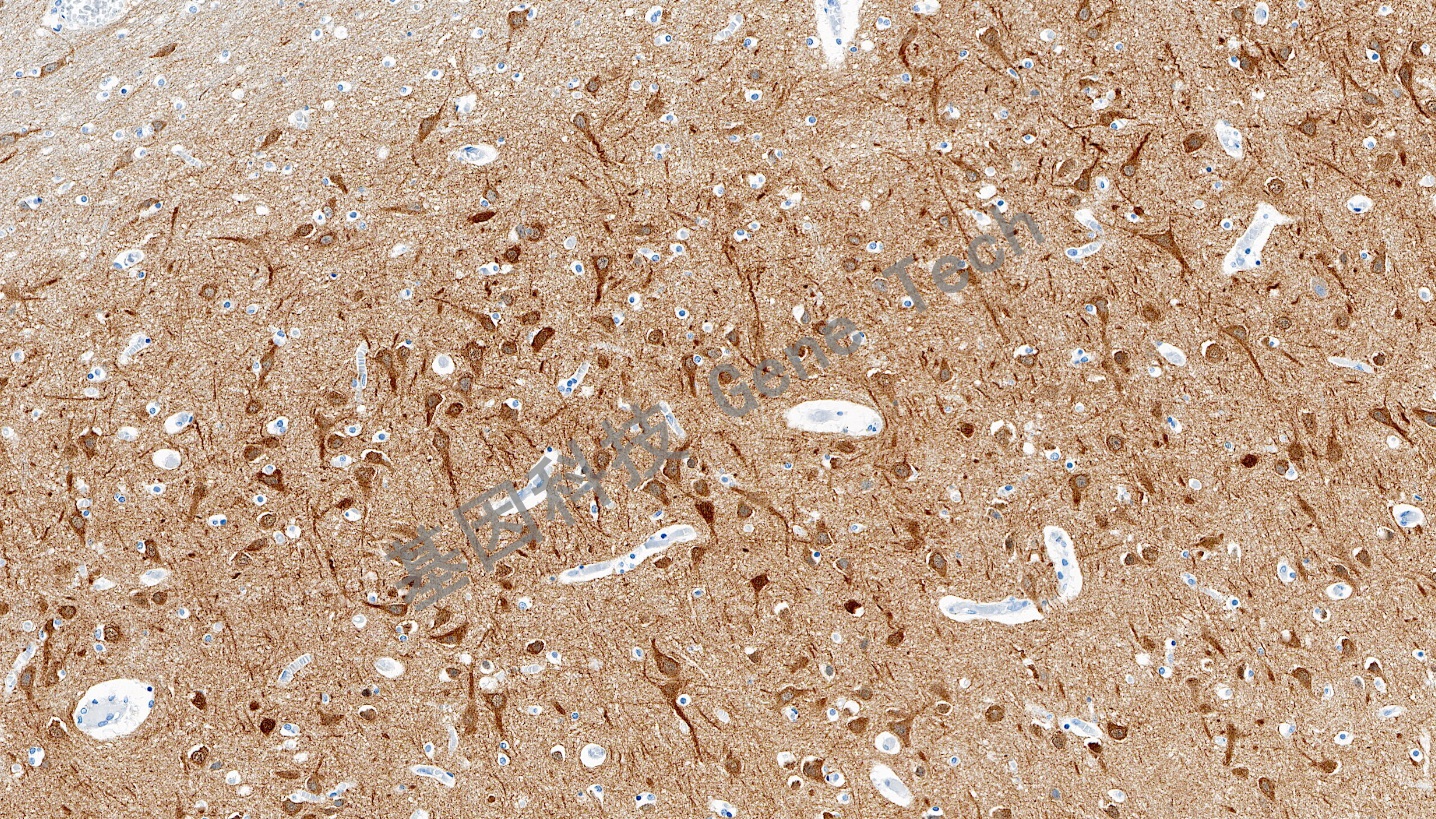

| 腦石蠟切片,用 DCLK1(GT2565)染色,細胞膜/細胞漿陽性,DAB 顯色。 | ||

| 預處理:高pH熱修復 | 陽性部位:細胞膜/細胞漿 | 陽性對照:腦 |